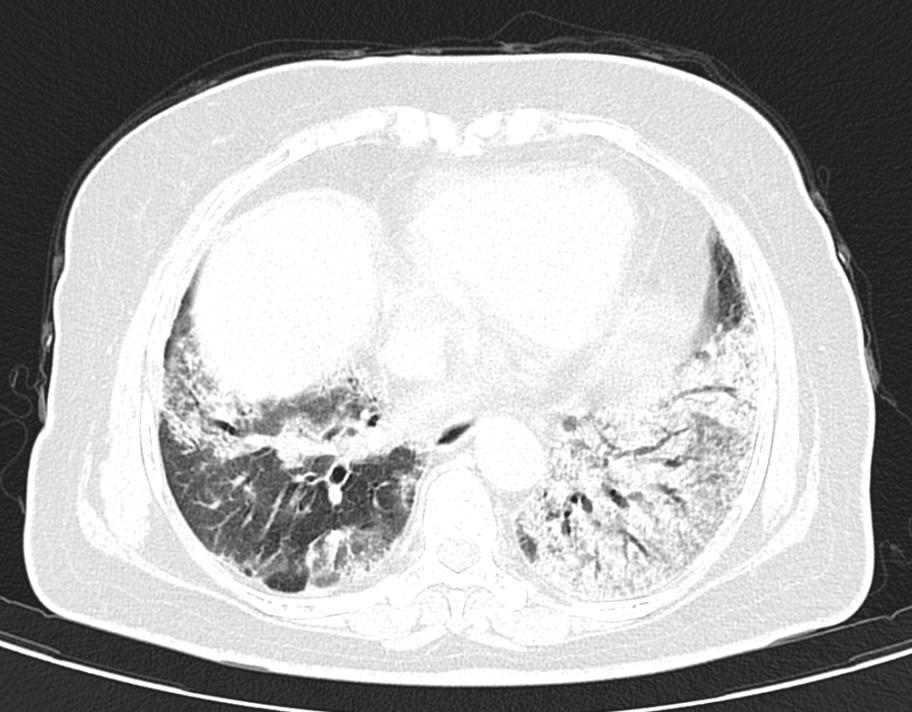

魏风芹对患者进行了详细病史询问及查体,结合患者院外的治疗过程、CT检查结果以及治疗后临床症状和肺部CT的进展情况,考虑“机化性肺炎可能性大”。但要明确诊断,就必须进行一些有创性操作,如肺穿刺活检或支气管镜检查,然而由于患者就诊时间较晚,肺底部已经出现纤维化,肺穿刺出现气胸的风险很大;而患者不动都感觉憋气,气管镜检查也面临着巨大挑战。

冷冻肺活检技术要求高,风险大,为确保手术顺利进行,支气管镜室配备了两位麻醉医师、三位护士,提前做好了充分的准备工作,并联系本部病理科做好活检组织的病理分析工作。最终,经过呼吸与危重症医学科、麻醉科及病理科的通力协作下,确诊该患者罹患一例罕见的“纤维化型机化性肺炎”。经治疗,患者症状好转并顺利出院。